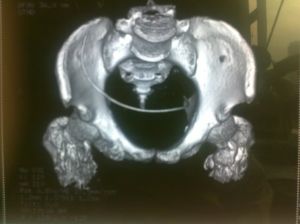

異位骨化是指在軟組織出現成骨細胞,並形成骨組織。多半發生在大關節周圍,例如髖關節、肘關節等。常見於神經癱瘓的患者。發病機理不清楚。誘發因素可能是神經和生物電因素。早期局部有明顯腫痛,關節活動受限。晚期由於骨組織形成,導致關節活動限制。

病因 臨床表現 檢查 參考資料,術後功能恢復快,異位骨化形成少,關節活動滿意,但此入路解剖複雜,要防止損傷...相似,但損傷較小,異位骨化發生率較低。髖臼骨折手術復位內固定治療的方法...創傷性關節炎的發生。 異位骨化術後發生了異位骨化,但程度較輕,髖關節的屈曲...